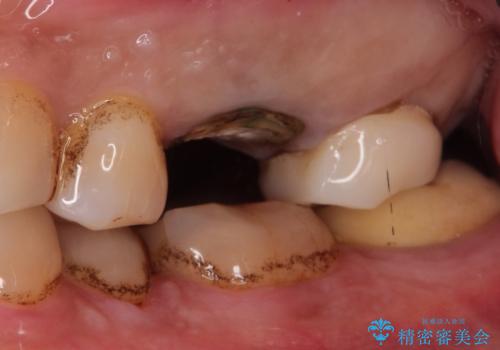

【歯牙破折】インプラントによる咬合回復

- 痛みを主訴に来院されました。

歯牙の破折を認めたため抜歯をし、インプラントにて咬合回復をしました。

抜歯後、骨増生を行ったのちインプラントを埋入しています。